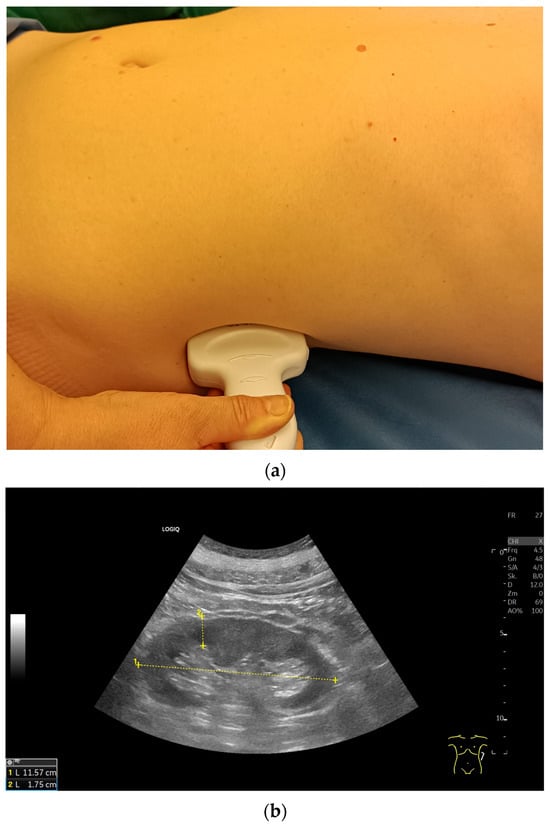

Variability of Renal Ultrasound Measurements: How Physician Experience and Patient Position Affect Measurement Accuracy?

J. Clin. Med. 2025, 14(16), 5840; https://doi.org/10.3390/jcm14165840 - 18 Aug 2025

This study was designed to investigate the variability of renal ultrasound measurements, focusing on the impact of physician experience and patient position. Background: Since decreased kidney length is considered an indicator for chronic renal disease, understanding measurement repeatability and reproducibility is crucial [...] Read more.

This study was designed to investigate the variability of renal ultrasound measurements, focusing on the impact of physician experience and patient position. Background: Since decreased kidney length is considered an indicator for chronic renal disease, understanding measurement repeatability and reproducibility is crucial for establishing effective diagnostic guidelines. Methods: Fifty healthy young adults underwent renal ultrasound scans performed by three examiners with varying levels of experience (12 years, 5 years, and 4 weeks). Renal length was measured at the level of the hilum in three patient positions: supine, lateral decubitus, and prone, using a 2–6 MHz convex probe (GE Logiq S8). Results: This study found that examiner experience significantly affected the results of sonographic measurements. However, the Interclass Correlation Coefficient analysis for all examiners demonstrated good reliability in most positions, with the highest values observed for the prone position. Measurements in the lateral decubitus position showed highest values, especially for the most experience examiner. The less experienced sonographers produced more variable results. Conclusions: Standardized patient positioning improves the accuracy and reproducibility of renal ultrasound measurements. The prone position offers a balance of reliability and practicality, especially for less experienced operators. Full article